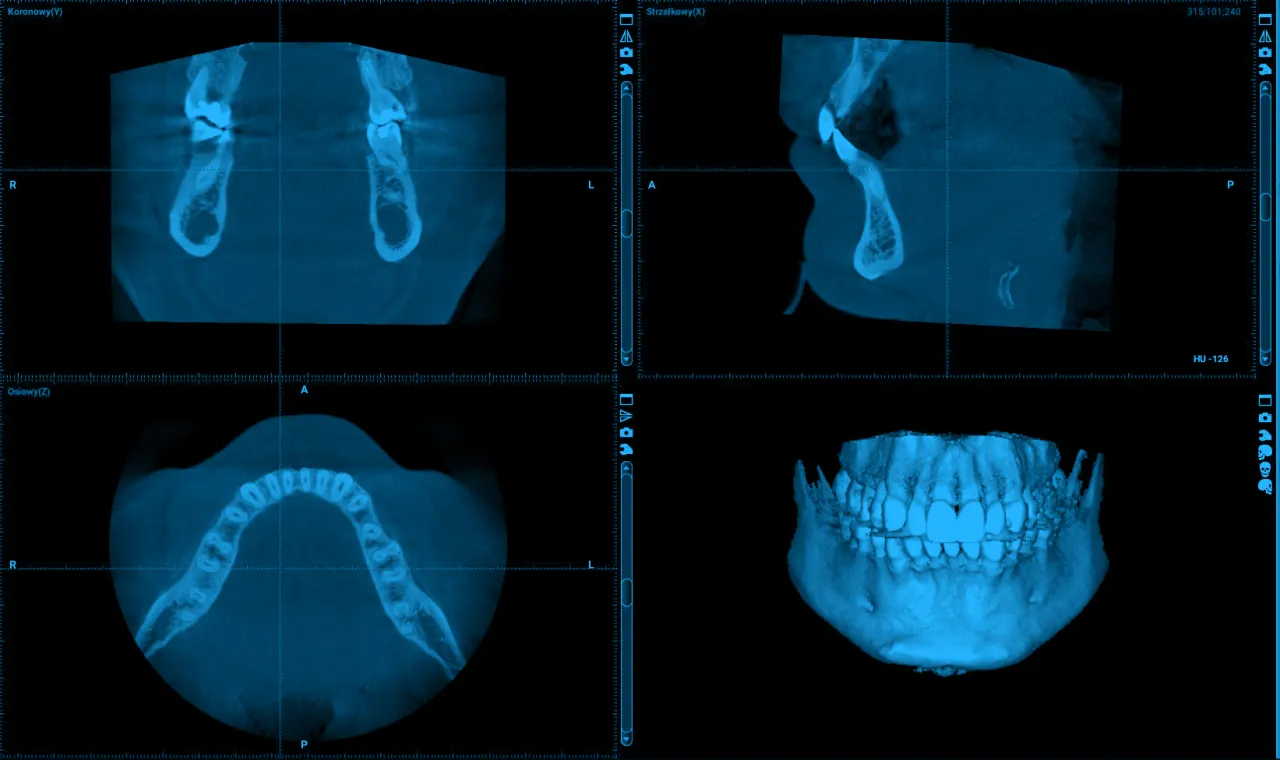

Diagnostyka radiologiczna jest nieodzownym elementem w przypadku zębów rosnących poza łukiem. Podstawą jest zazwyczaj zdjęcie pantomograficzne (OPG), które daje ogólny obraz wszystkich zębów i kości szczęk. Pozwala ono ocenić położenie zęba, jego korzeni oraz relacje z sąsiednimi strukturami. W bardziej skomplikowanych przypadkach, gdy potrzebujemy trójwymiarowego obrazu, niezbędna staje się tomografia komputerowa wiązki stożkowej (CBCT). CBCT pozwala na niezwykle dokładną ocenę położenia zęba, jego bliskości do nerwów, zatok czy innych ważnych struktur, co jest kluczowe dla bezpiecznego zaplanowania leczenia.

W takich przypadkach diagnostyka CBCT jest kluczowa, aby dokładnie zaplanować chirurgiczne usunięcie lub, w niektórych sytuacjach, ortodontyczne "sprowadzenie" zęba.